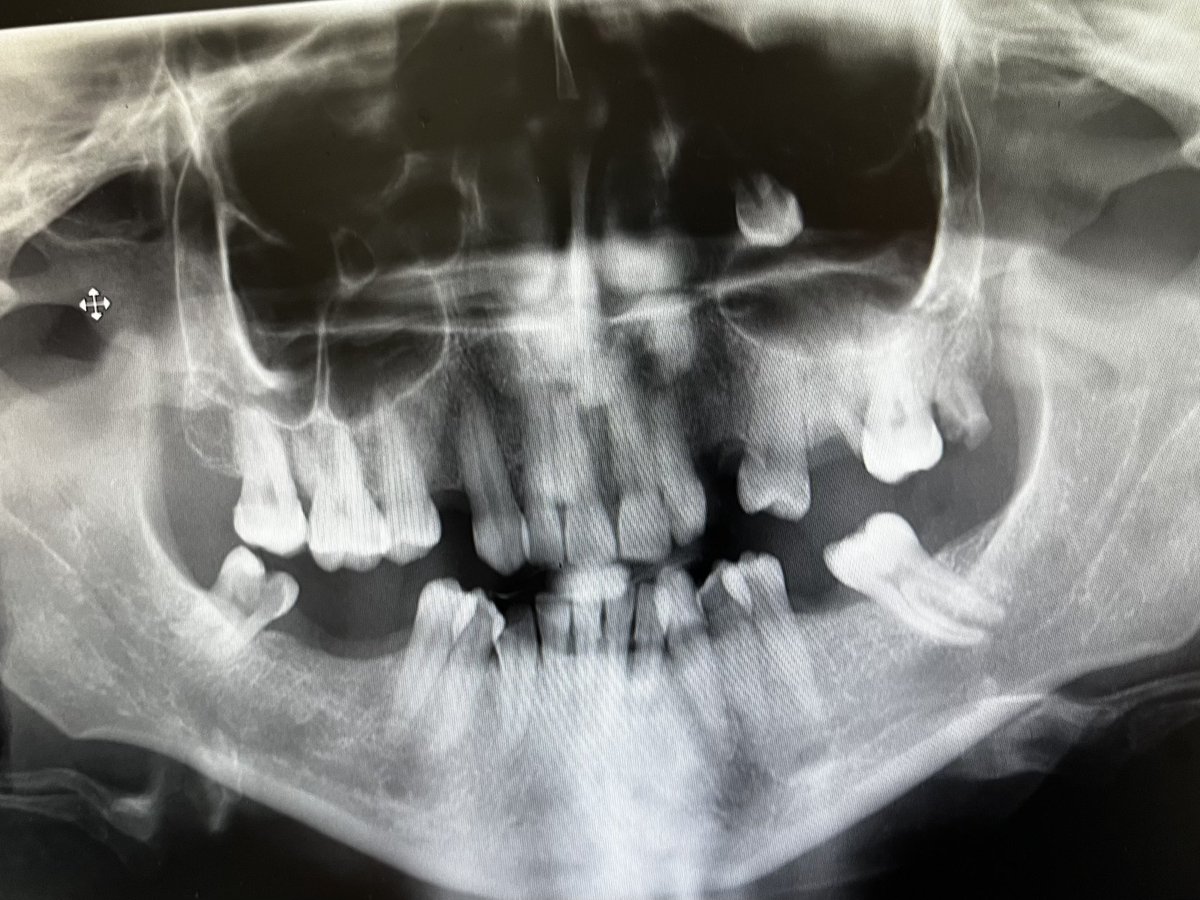

Op Dr Abdulkerim Karaaslan